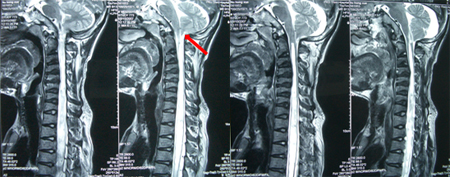

男性,35岁,自幼颅颈、双肩发育异常,双手、上肢肌萎缩3年,加重1月,伴走路不稳。查体:短颈、发髻低、双肩狭小畸形、脊柱侧弯,双上肢及躯干片状感觉障碍,双上肢肌力3-4级,远端更差伴双手爪形,双侧手指伸直困难,双侧病理征阳性。术前影像学资料显示:颅底凹陷、寰枕融合、颈椎生理曲度消失伴退行性改变,小脑扁桃体下疝入椎管伴脊髓空洞(达T8水平)。

术式:枕颈减压、枕大池成型、局限性椎板咬除减压、空洞穿刺引流术。术后可平稳行走,感觉障碍改善,术后半年肢体肌力改善。

专家评点:寰枕畸形尤其以颅底凹陷、寰枕融合为主常导致后颅窝的先天性狭小,随着脑组织的发育、成熟,和狭小后颅窝之间的矛盾逐渐显现并激化,挤压小脑扁桃体向下移位,从而卡压在颅颈交界、压迫延颈髓,导致脑脊液循环障碍,可出现梗阻性脑积水或脊髓空洞症。有学者提出针对无症状寰枕畸形采取手术治疗的观点,虽然这一观点有待进一步商酌,但从另一角度说明对寰枕畸形争取早日手术治疗的必要性。